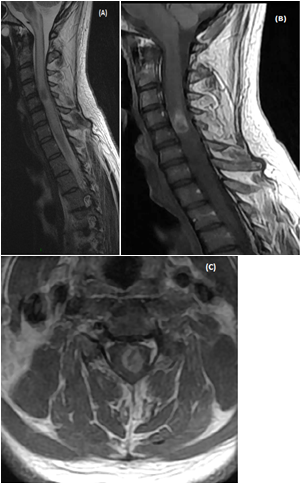

On blood testing at admission the complete blood count, comprehensive metabolic panel, inflammatory markers such as C-reactive protein level were normal. Brain MRI was normal. Spinal cord MRI showed cord enlargement at C4-C5 level and diffuseT2-images high signal from medulla to T4 level. A central area of necrosis hypointense was found on T1-images at C4-C5 level with peripheral enhancement after contrast (Figures 1A-1C). Together, these MRI findings were suggestive of an ISCA. Diffusion weighted images (DWI) showed hyposignal consistent with restricted diffusion on ADC map in the area of the necrotic portion of the cordlesion (Figures 1D&1E).

Figure 1 MRI of an intramedullary cervical spinal cord abscess.

(A) T2-weighted sagittal view of the cervical spine shows intramedullary hyper signal intensity from medulla to T4 level together with expansion of the spinal cord, consistent with edema. Note the central area of necrosis at C4-C5 level. T1-weighted sagittal (B) and axial (C) post-contrast images, showring-enhancement of the lesion at C4-C5 level. The vertebral bodies are intact without disc space infection, epidural collection, or sub dural empyema. (D)The enhancing part of the lesionis slighly hyper intense on sagittal Diffusion-weighted (DW)« focus » sequence (E) Restricted diffusion is visible as a dark dot inside the necrotic area on ADC map (arrow). Follow-up MRI of cervical spine (T1-weighted sagittal (F) and axial (G) post-contrast images performed 14 days after initiation of antibiotic treatment shows partial resolution of the lesion. h -At 6 month-MRI follow-up the lesion has disappeared.